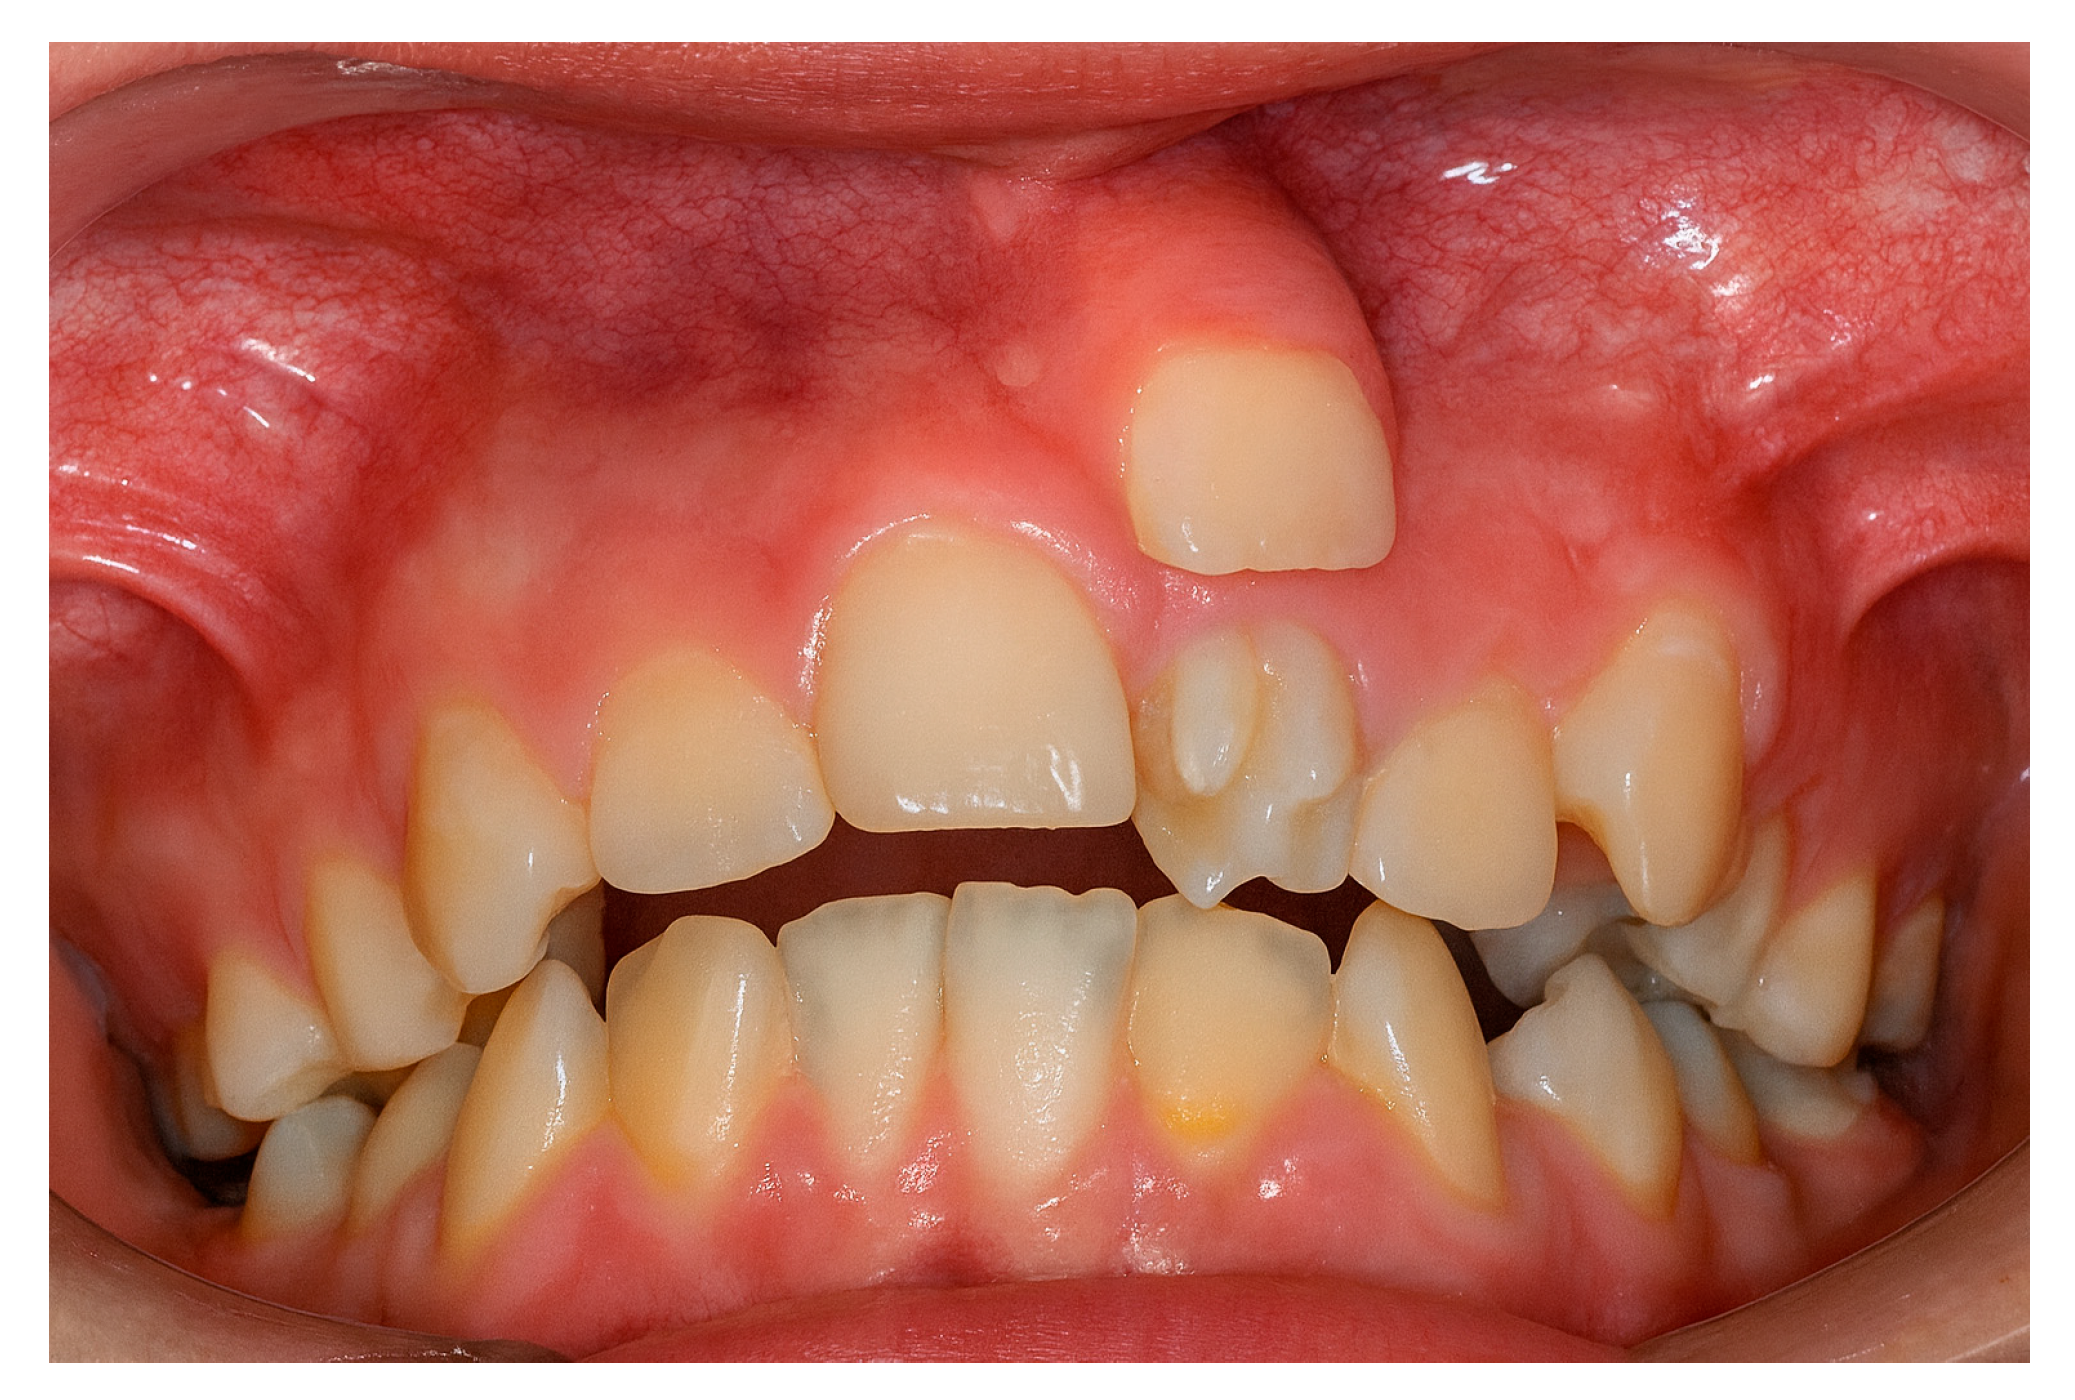

The presence of supernumerary teeth (Figure 1) is not a morphological curiosity but a potential source of diverse pathological complications [1,2,3,4].

Figure 1. Supernumerary teeth in the upper left quadrant.